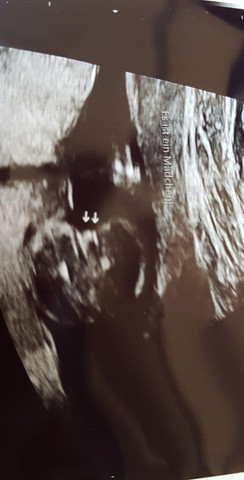

Hallo Ihr Lieben, für alle UltraschallGeschlechtserkennerExperten unter Euch Erkennt man auf dem US schon das Geschlecht des Baby?.

SSW (Schwangerschaftswoche) Dein Baby, dein Körper, Beschwerden und mehr;. Ich hätte eine Frage und zwar war ich bei 196 SSW zum 2 Screening Dort habe ich erfahren das mein Baby ein Mädchen wird} Nun habe ich schon angefangen Kleidchen ect zu kaufen Da mein Gyn sich sehr sicher war das es ein Mädchen wird. Das Bild wurde Ende der 9 SSW (86) gemacht Kann man da überhaupt schon das Geschlecht erkennen?.

Ich bin Ende der ssw und hier ist das heutige Ultraschallbild was die Geschlechterfrage angeht meine Frauenärztin war sich relativ sicher Bitte euch um Erfahrungswerte ob ihr meint dass wir uns wirklich auf rosa einstellen können/ dürfen. Dein Baby in der SSW Eigentlich ein Wunder, wie aktiv Babys trotz Platzmangel in Mamas Bauch doch sein können!. Die SSW ist für Ihr Baby wieder ein wichtiger Meilenstein, denn nun dreht sich alles um die weitere Ausbildung der Sinne Immer besser bilden sich der Geruchssinn und der Geschmackssinn, der Tastsinn, das Gehör sowie das Sehvermögen heraus.